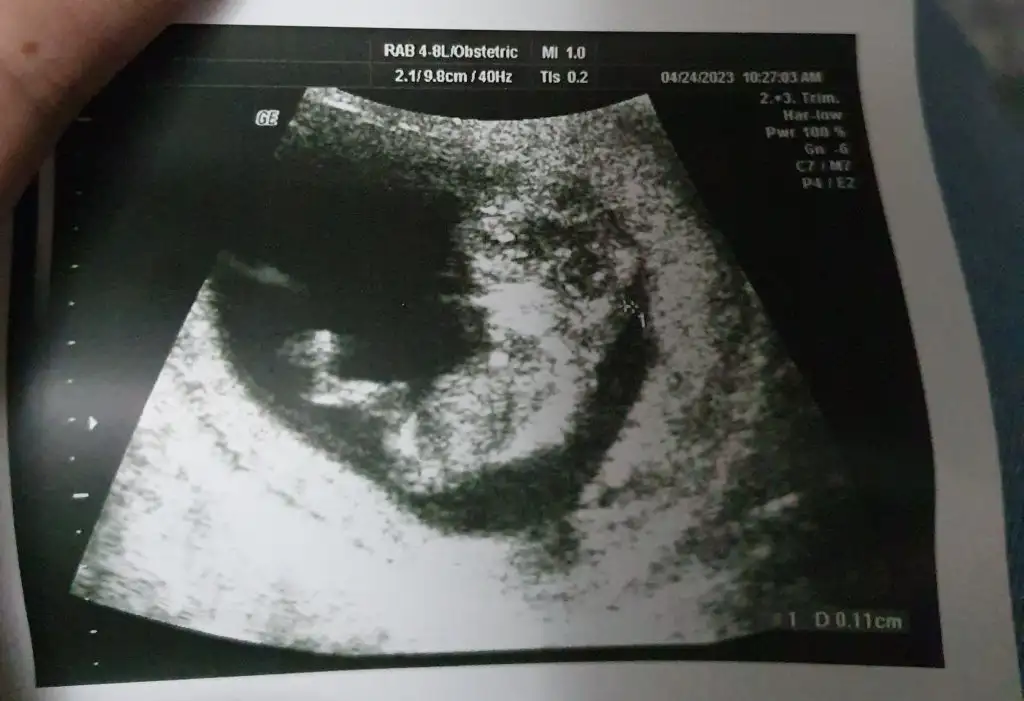

Canım nubu tam belli değil, bebeğin açısından kaynaklı olarak. Gönlündeki olur inşallahKızlar 11artı 4 olmuşuz bugün doktora gittim. Bir kez daha cinsiyet tahmini yapar mısınız? Karından ultrason görüntüsü.

Eki Görüntüle 3237493

Evet yaa kafa şekline göre kız duruyor ama bakalım. Gönlümden kız geçiyorCanım nubu tam belli değil, bebeğin açısından kaynaklı olarak. Gönlündeki olur inşallah

Ben de kız hissettim bu aradaEvet yaa kafa şekline göre kız duruyor ama bakalım. Gönlümden kız geçiyorgeçen sefer kız denmişti burada da